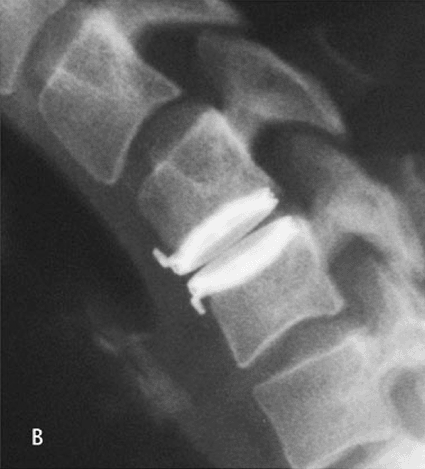

PEEK Interbody Device Allows Simpler Spinal Fusion Procedures